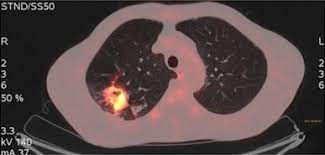

Concomitant active tuberculosis in nsclc (tblc) resembles locoregional immunotherapy of tumor cell vaccine;

Difference between lung cancer and tuberculosis. This growth can spread beyond the lung by the process of metastasis into nearby tissue or other parts of the body. Selection of the most suitable tests for detection of m. However, this can also occur with tuberculosis or a pulmonary embolism. Concomitant active tuberculosis in nsclc (tblc) resembles locoregional immunotherapy of tumor cell vaccine; Primary tuberculosis clinical forms the primary site of infection in the lungs is called the ghon focus. Living with advanced breast cancer. Symptoms of tuberculosis and lung cancer are overlapping and it is difficult to differentiate without the histopathological report. When people with lung tb cough, sneeze or spit, they propel the tb germs into the air. Lung cancer and pulmonary tuberculosis (tb) comorbidity is a clinical problem that presents a challenge for the diagnosis and treatment of both diseases.objective: Tuberculosis (tb) is a potentially serious infectious disease that mainly affects the lungs. Primary tuberculosis usually begins in childhood and affects the lungs and bronchial lymphatic glands of the lung roots. You can't get it from shaking hands with someone who has it or by sharing their food or drink.

Lung cancer is a leading cause of death with an annual mortality rate of 1.59 million people, accounting for 19.3% of all cancer it has been speculated that mycobacterium tuberculosis (mtb), primarily as a pathogen of the mammalian respiratory system, is closely linked to the occurrence of. Lung cancer and pulmonary tuberculosis (tb) comorbidity is a clinical problem that presents a challenge for the diagnosis and treatment of both diseases.objective: Lung cancer is often divided into two types: You can get tb by breathing in air droplets from a cough or sneeze of an infected person. Pulmonary tb is caused by the bacterium mycobacterium tuberculosis (m tuberculosis). Concomitant active tuberculosis in nsclc (tblc) resembles locoregional immunotherapy of tumor cell vaccine; 90% of cases being attributable to smoking. However, this can also occur with tuberculosis or a pulmonary embolism. Tuberculosis infection should be based on the reasons and the context for testing, test availability, and overall cost. This growth can spread beyond the lung by the process of metastasis into nearby tissue or other parts of the body. Patients with lung cancer are often misdiagnosed as pulmonary tuberculosis leading to delay in the correct diagnosis as well as exposure to inappropriate. Tuberculosis germs don't thrive on surfaces. Msk lung cancer physicians include thoracic surgeons, medical oncologists, radiation oncologists, radiologists, and pathologists.

Selection of the most suitable tests for detection of m. Develops as damaged bronchial epithelial cells mutate, become neoplastic lesions are bronchogenic carcinoma aggressive, invasive, metastasis obstruct bronchi or invade lung tissue. In the past, it was well known that lung cancer is a specific epidemiological successor of ptb and that lung cancer often develops in scars caused by ptb. Pleural effusion may develop in lung cancer, breast cancer, lymphoma, lymphogranulematosis, benign and malignant pleural mesothelioma, bacterial 3.2. It is most commonly caused by aspiration of oral secretions by patients who have impaired consciousness. Tb and lung cancer have been confused and misdiagnosed for centuries 2. There is especially in countries with low tb incidence diagnostic challenges with risk of diagnosis getting missed. The occurrence of pulmonary tuberculosis (ptb) and lung cancer as comorbidities has been extensively discussed in many studies. Why has this disease, once thought to be confined to the. This means the bacteria are easily spread from an infected person to someone else. This is one reason that it is among the most deadly of cancer groups. Symptoms of tuberculosis and lung cancer are overlapping and it is difficult to differentiate without the histopathological report. Methods retrospective review of nsclc.